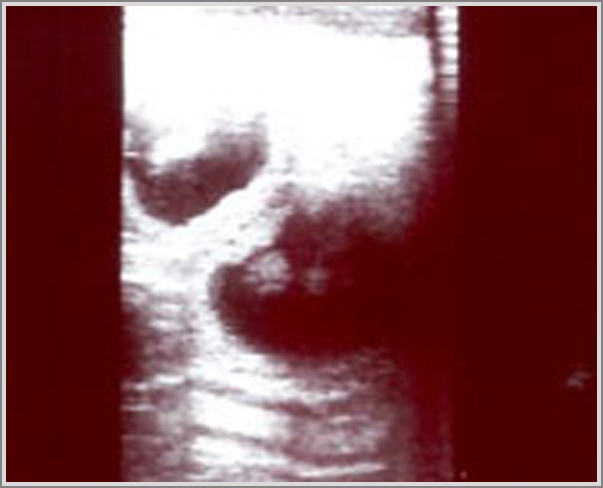

18.09.12

28. Tag

Heute ist der beste Zeitpunkt, um die Trächtigkeit per Ultraschall nachzuweisen.

!!!JUHU Es hat geklappt Inara ist trächtig!!!